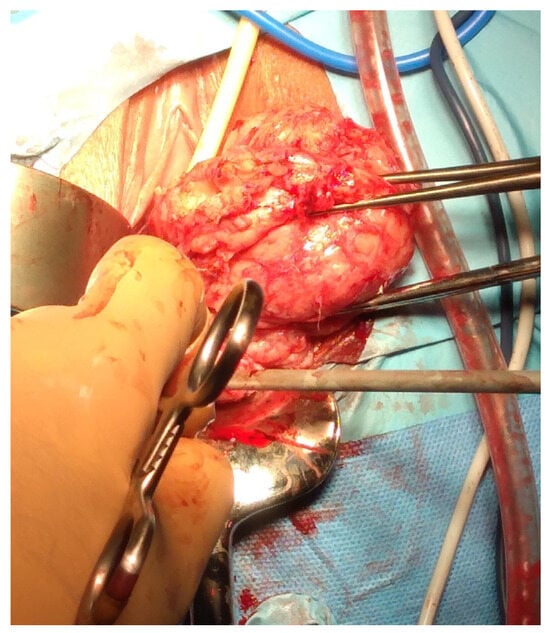

The intracapsular myomectomy may be executed through various approaches, including laparotomy (Figure 8), laparoscopy, robotic assistance, vaginal access (Figure 9), and hysteroscopy.

Figure 8.

Laparotomic image of intracapsular myomectomy. The surgeon enucleates a large fibroid measuring over 15 cm, gradually detaching it from the uterus by sectioning bundles of pseudocapsule that anchor it to the uterus. Minimal bleeding is noted during myomectomy.